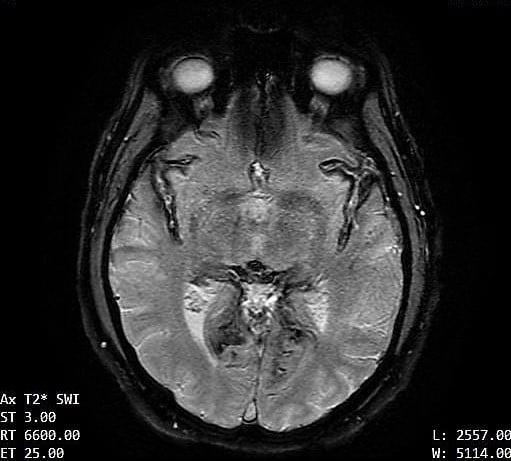

The contours of the cerebrum, cerebellum, and brainstem are outlined with a T2 hypointense signal with blooming on susceptibility weighted sequences, which is compatible with the clinical history of superficial siderosis. A majority of the T2 hypointense signal is present in the superior folia of the cerebellum but also seen coating the surfaces of the brainstem, the cortical surfaces along the Sylvian fissures, and the cortical surfaces of the paramedian sulci of the frontal and occipital lobes. Few subcortical and periventricular T2/FLAIR hyperintensities are present in both cerebral hemispheres.²

If you look at each image, you can see the dark areas where his hemosiderin deposits are. The radiologist will use the same machine and settings, so we should visually compare the new images with these for some positive change.³